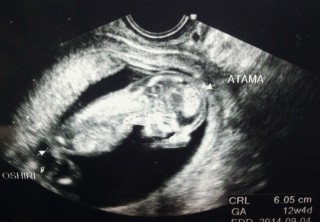

こんなにハッキリ見えて感動!もしかして男の子なのかな??元気に足を屈伸したりバタバタと動いていたので落ち着きのない子だねって笑顔で言われてしまいました。。。笑 とっても可愛くって既に親バカです。

01週間分も大きめでした(^^)